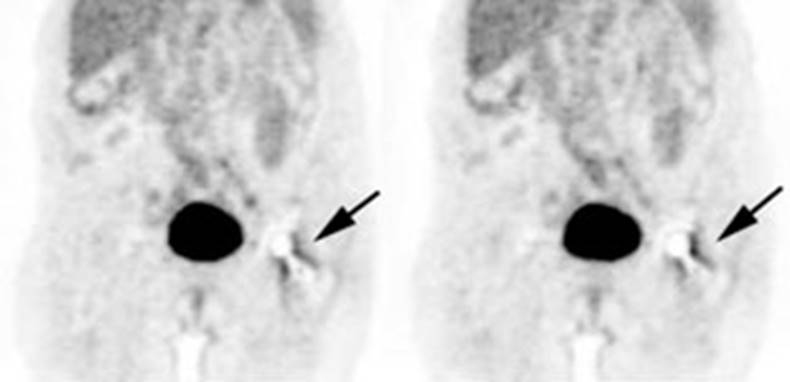

Figure 21 - Marrow activity: The images below are from

two separate patients each showing mild FDG accumulation within the vertebral

bodies.